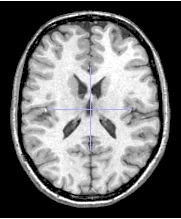

Selection of threshold : a image is composed with grey levels from 0 to 4095 (for example image). The grey level '0' is in fact black color and the '4095' is white color, all others grey levels are between 1 and 4094. To know the minimun and the maximun of grey level, you can put your image in a browser in Anatomist and read tex_min (black) and tex_max (white) attributes. To handle grey levels of your image, use ROI module of Anatomist (option Connectivity Threshold).

Test image, tex_min = 0, tex_max = 4095